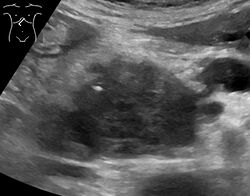

Medical imaging techniques, such as computed tomography (CT scan) and endoscopic ultrasound (EUS) are used both to confirm the diagnosis and to help decide whether the tumor can be surgically removed (its "resectability").[12] On contrast CT scan, pancreatic cancer typically shows a gradually increasing radiocontrast uptake, rather than a fast washout as seen in a normal pancreas or a delayed washout as seen in chronic pancreatitis.[56] Magnetic resonance imaging and positron emission tomography may also be used,[2] and magnetic resonance cholangiopancreatography may be useful in some cases.[32] Abdominal ultrasound is less sensitive and will miss small tumors, but can identify cancers that have spread to the liver and build-up of fluid in the peritoneal cavity (ascites).[12] It may be used for a quick and cheap first examination before other techniques.[57]